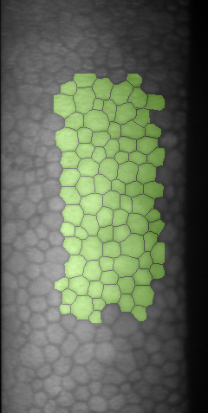

Specular microscopy assessment of the human corneal endothelium (CE) in Fuchs' dystrophy is challenging due to the presence of dark image regions called guttae. This paper proposes a UNet-based segmentation approach that requires minimal post-processing and achieves reliable CE morphometric assessment and guttae identification across all degrees of Fuchs' dystrophy. We cast the segmentation problem as a regression task of the cell and gutta signed distance maps instead of a pixel-level classification task as typically done with UNets. Compared to the conventional UNet classification approach, the distance-map regression approach converges faster in clinically relevant parameters. It also produces morphometric parameters that agree with the manually-segmented ground-truth data, namely the average cell density difference of -41.9 cells/mm2 (95% confidence interval (CI) [-306.2, 222.5]) and the average difference of mean cell area of 14.8 um2 (95% CI [-41.9, 71.5]). These results suggest a promising alternative for CE assessment.